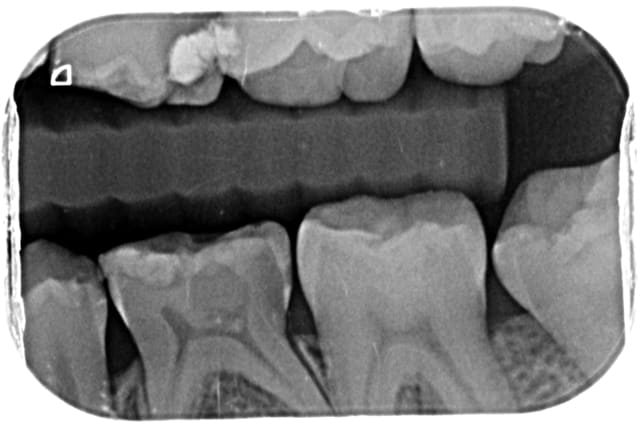

je reçois ce jour cette nouvelle patiente trisomique qui présente des agénésies multiples.

55,65,75 et 85 ont été conservées

mais pour 65 75 et 85 c'est endo je pense

je pense faire reconstitution avec tenon fibré et couronne

je crois que c'est npc en tout cas pour la couronne.

Si l'état pulpaire le permet, je pencherai plutôt pour de simples pulpotomies bien faites.

Puis reconstitution en fonction du délabrement, je suis plutôt favorable aux coiffes pédo, bien bouterollées en sous-gingival. Cela permettra probablement de gagner pas mal de temps avant les implants.

Le délabrement sur 65 et encore plus sur 75 seront plus qu'occluso-proximaux

La restauration directe ou indirecte ne concernera que 85 dans le meilleur des cas.